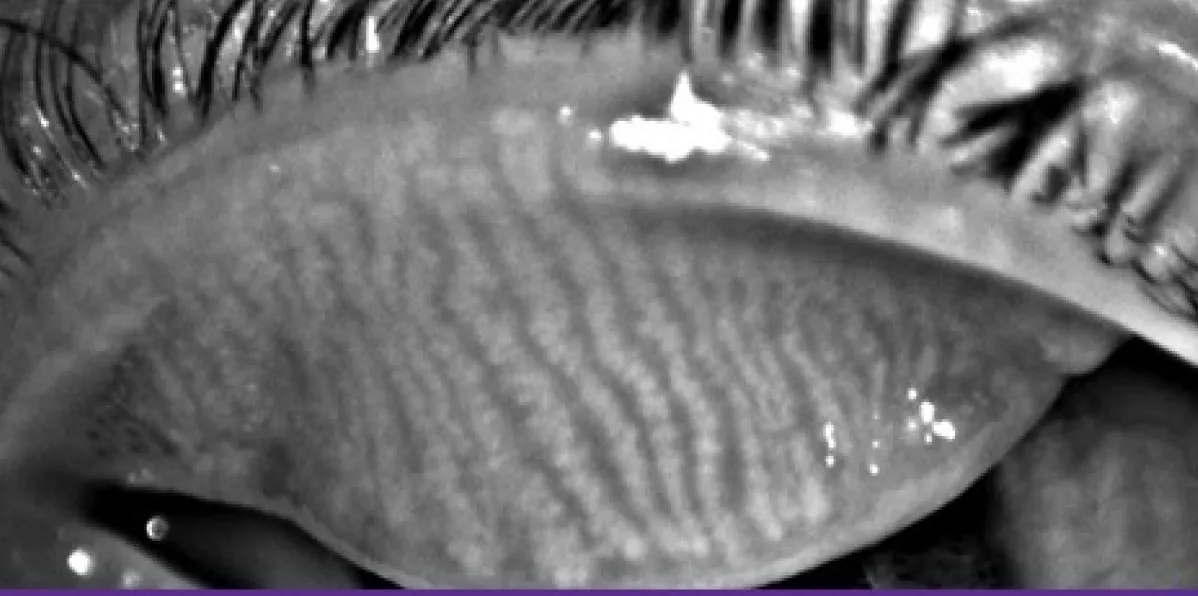

Meibography uses advanced imaging to evaluate the health of the meibomian glands, which produce the oils that prevent tears from evaporating too quickly. This test is essential for diagnosing evaporative dry eye and gland dysfunction, allowing targeted treatments that improve tear stability, comfort, and vision quality.

Close-up image of eyelid showing tear film pattern during exam